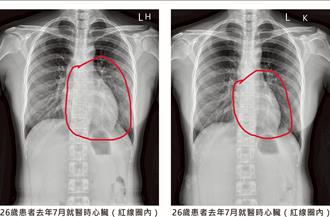

• 沒喘沒胸悶!妙齡女X光揭心臟衰竭 竟是甲狀腺亢進惹禍

沒喘沒胸悶!妙齡女X光揭心臟衰竭 竟是甲狀腺亢進惹禍

彰化1名26歲妙齡女子平日並無喘或胸悶等症狀,但去年健檢時,經由X光片發現心臟較擴大,經檢查發現女子左心室射出分率只有39%,員榮醫療體系員榮醫院心臟內科主任陳裕峰表示,女子已符合心臟衰竭定義,追查後發現女子有甲狀腺家族病史,經按時服藥近10個月後,如今已痊癒。